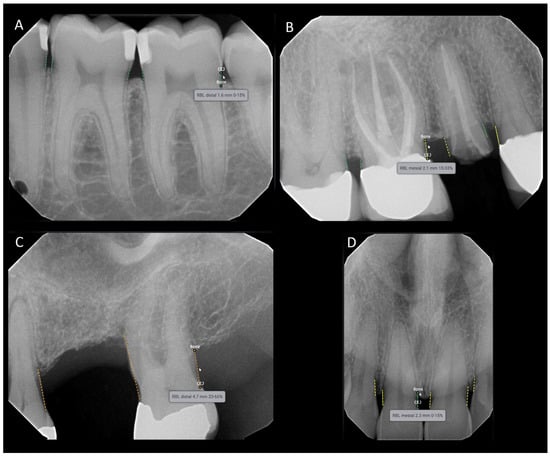

2.3. The Deep Learning Software, Definition of RBL Used, and Reference Standard